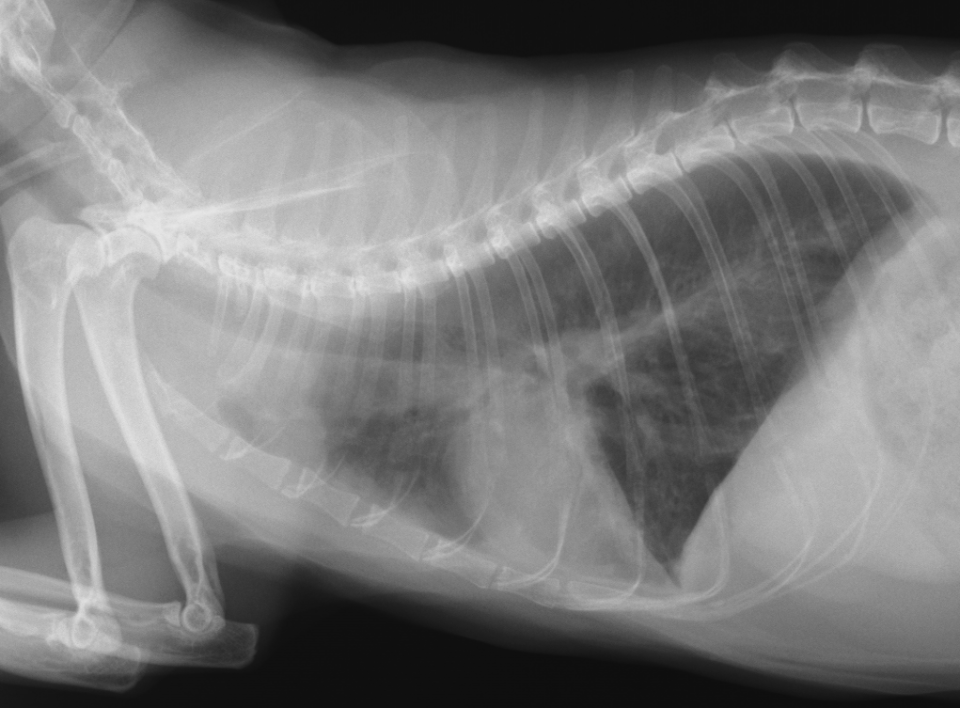

わんちゃんの巨大食道症。食道炎から二次的に起きる場合や、重症筋無力症の症状として発症する場合があります。合併症の誤嚥性肺炎の危険性があり、食後の立位の維持や少量ずつの食事などの看護が必要です。

重度な巨大食道と誤嚥性肺炎のわんちゃん

わんちゃんの巨大食道症。食道炎から二次的に起きる場合や、重症筋無力症の症状として発症する場合があります。合併症の誤嚥性肺炎の危険性があり、食後の立位の維持や少量ずつの食事などの看護が必要です。

重度な巨大食道と誤嚥性肺炎のわんちゃん